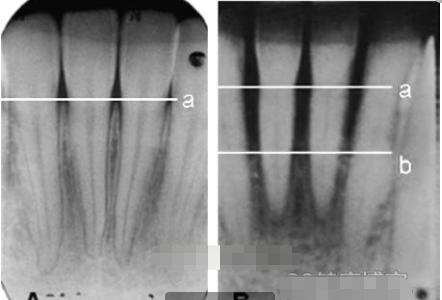

牙槽骨的吸收分为,水平吸收,垂直吸收和混合吸收三个类别。

- 水平吸收就是牙槽骨的整体高度发生下降,每一个牙根在牙槽骨中的部分都有减少。

- 垂直吸收就是牙槽骨发生斜向或者垂直方向的吸收,高度降低不多但是牙根部位会有比较明显的吸收现象。